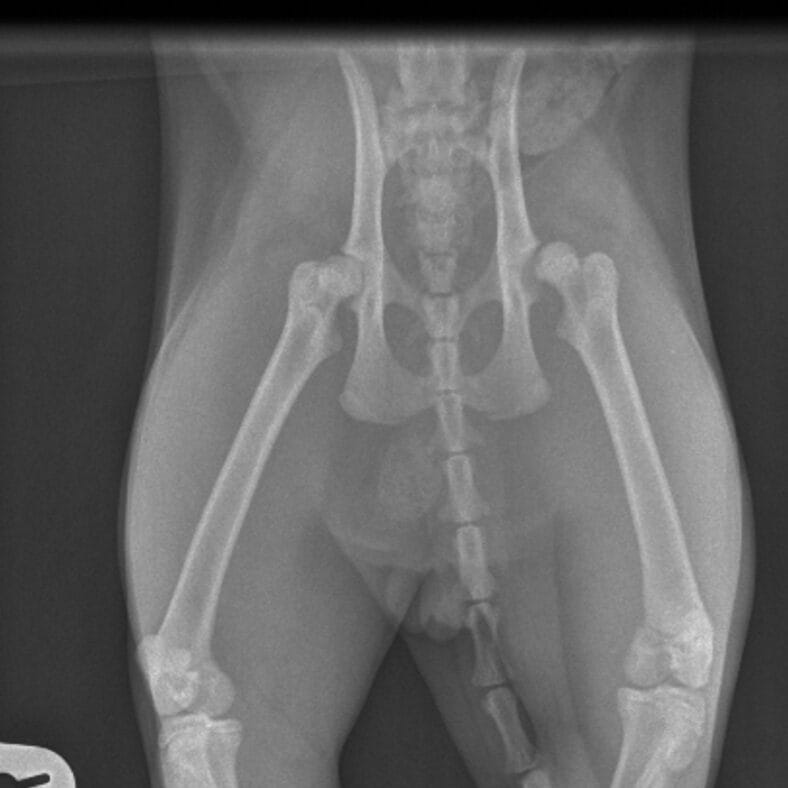

A fractured femur. A broken leg. A chest injury. A limp tail. A pelvic fracture.

After a full examination, the veterinary team found that Benito’s spine had been fractured.